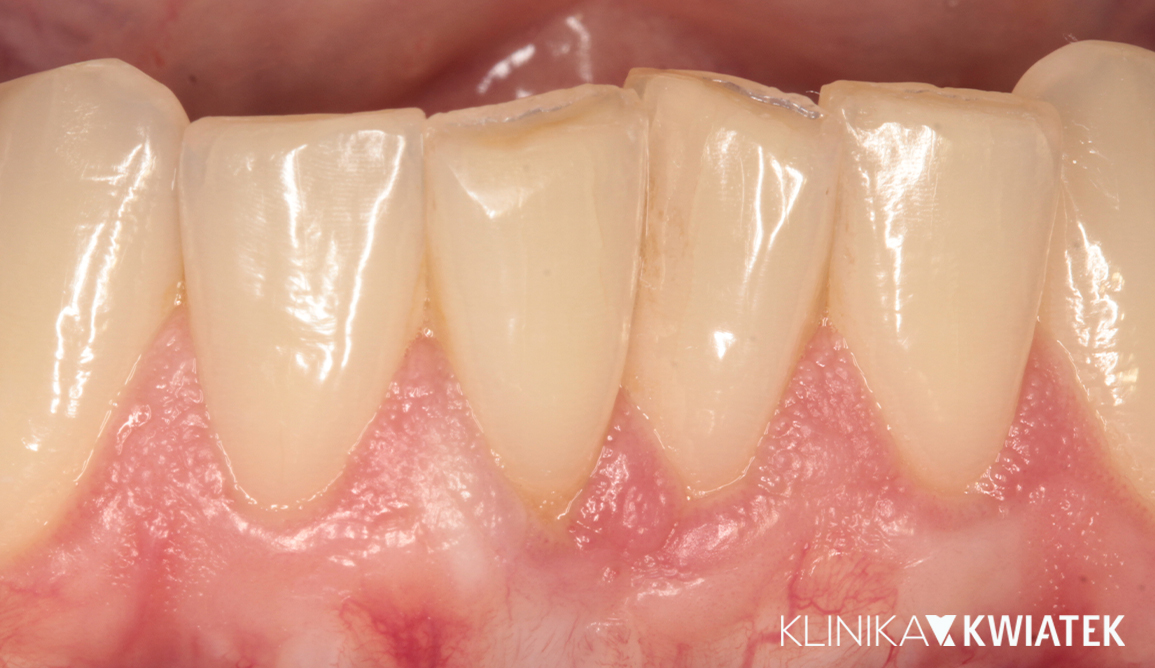

Od szparowatości do ideału – siła bondingu w estetyce

Pacjentka zgłosiła się z problemem bólu stawów skroniowo-żuchwowych, zgrzytania zębami oraz przerw między siekaczami. Po dokładnej diagnostyce wdrożono szynoterapię, leczenie ortodontyczne przezroczystymi nakładkami, a następnie odbudowy estetyczne i retencję. Efektem jest stabilny zgryz, komfort w codziennym funkcjonowaniu oraz harmonijny, naturalny uśmiech.